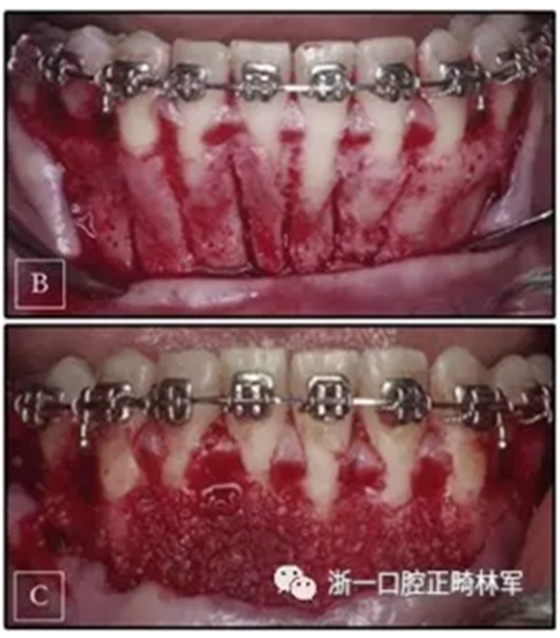

正畸矯治器放置后,將牙弓矯平并對(duì)齊。一旦這一階段完成,將下頜切牙區(qū)的唇側(cè)部分,即從左側(cè)尖牙到右側(cè)尖牙,進(jìn)行翻瓣,并放置凍干的骨移植物(圖4)。 手術(shù)后一周,制作一個(gè)長(zhǎng)方形不銹鋼的開(kāi)口環(huán),并在第一磨牙近中形成止點(diǎn),并放置以進(jìn)行深覆蓋的矯正。每7至10天對(duì)患者進(jìn)行評(píng)估以在完全骨再礦化之前激活矯正裝置。 在5個(gè)月內(nèi)完全糾正深覆蓋,并將臨時(shí)支抗裝置放置在下頜右側(cè)尖牙的遠(yuǎn)中,以使右側(cè)頰部部分向前移動(dòng)。 為了幫助這種前移,使用短的II類牽引。

圖4. A,手術(shù)計(jì)劃; B,選擇性壓力側(cè)翻瓣過(guò)程; C,植入材料。